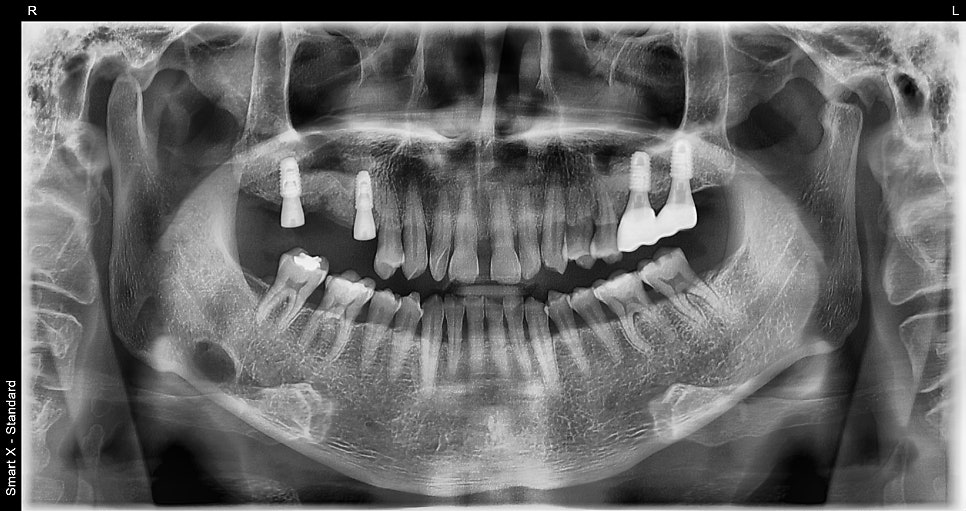

- 3월 중순: 2차 수술, 단추 (힐링어버트먼트) 연결

2차 수술 후 힐링어버트먼트 연결까지 완료된 상태의 파노라마 엑스레이입니다.

임플란트 식립 위치가 안정적으로 유지되고 있으며, 1차 수술 이후 잇몸 염증이나 부작용 없이 경과가 매우 우수했습니다.

- 4월 초~중순: 구강스캐너로 본 뜨기 → 최종 보철 장착 완료

왼쪽 사진: 최종 보철 장착 후 촬영한 파노라마 엑스레이입니다.

오른쪽 사진 : 치료가 마무리된 후의 구강 내 사진입니다.

보철물은 지르코니아 재료로 제작되어 단단하면서도 심미적이며, 자연치와의 조화가 뛰어나게 마무리되었습니다.

✔️ 고혈압, 당뇨, 흡연, 턱관절 장애 등 쉽지 않은 조건이었지만

정확한 진단 + 좋은 재료 사용 + 발치 당일 식립 + 잇몸치료 병행을 통해

단기간 내에 안정적인 결과를 얻을 수 있었습니다.